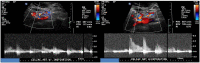

Median arcuate ligament syndrome (MALS), also known as celiac artery compression syndrome, is a rare gastrointestinal condition with an estimated incidence of 2 per 100 000 population. Predominantly in female patients, this syndrome is characterized by the compression of the celiac artery at its origin from the aorta by the median arcuate ligament, which at the same time is entrapping the celiac plexus, causing upper abdominal pain, notably postprandial pain, as well as nausea, vomiting, food aversion, and weight loss. We present a case of abdominal pain secondary to MALS that was appropriately diagnosed after requiring narcotic medication, which responded to surgical therapy.